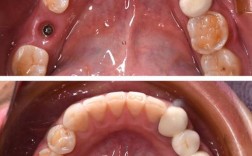

| 口腔局部评估 | CBCT/全景片(测量骨高度、厚度、密度)、牙周检查(探诊出血、牙周袋深度) | 评估骨量是否充足、有无牙周炎等基础疾病 |

| 口腔黏膜检查 | 观察有无溃疡、白斑、红斑,唾液分泌量(如Schirmer试验) | 确认黏膜愈合情况,排除活动性病变 |